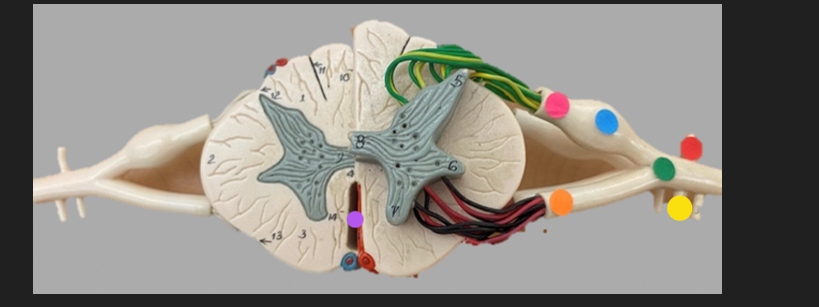

green dot

spinal nerve

orange dot

ventral root

pink dot

dorsal root

blue dot

dorsal root ganglion

red dot

dorsal ramus

yellow dot

ventral ramus

purple dot

anterior median fissure

red dot

posterior (dorsal) horn

purple dot

lateral horn

dark blue dot

anterior (ventral) horn

orange dot

dorsal column

yellow dot

lateral column

dark green

anterior column

line green and pink doit

gray commissure

light blue dot

posterior median sulcus